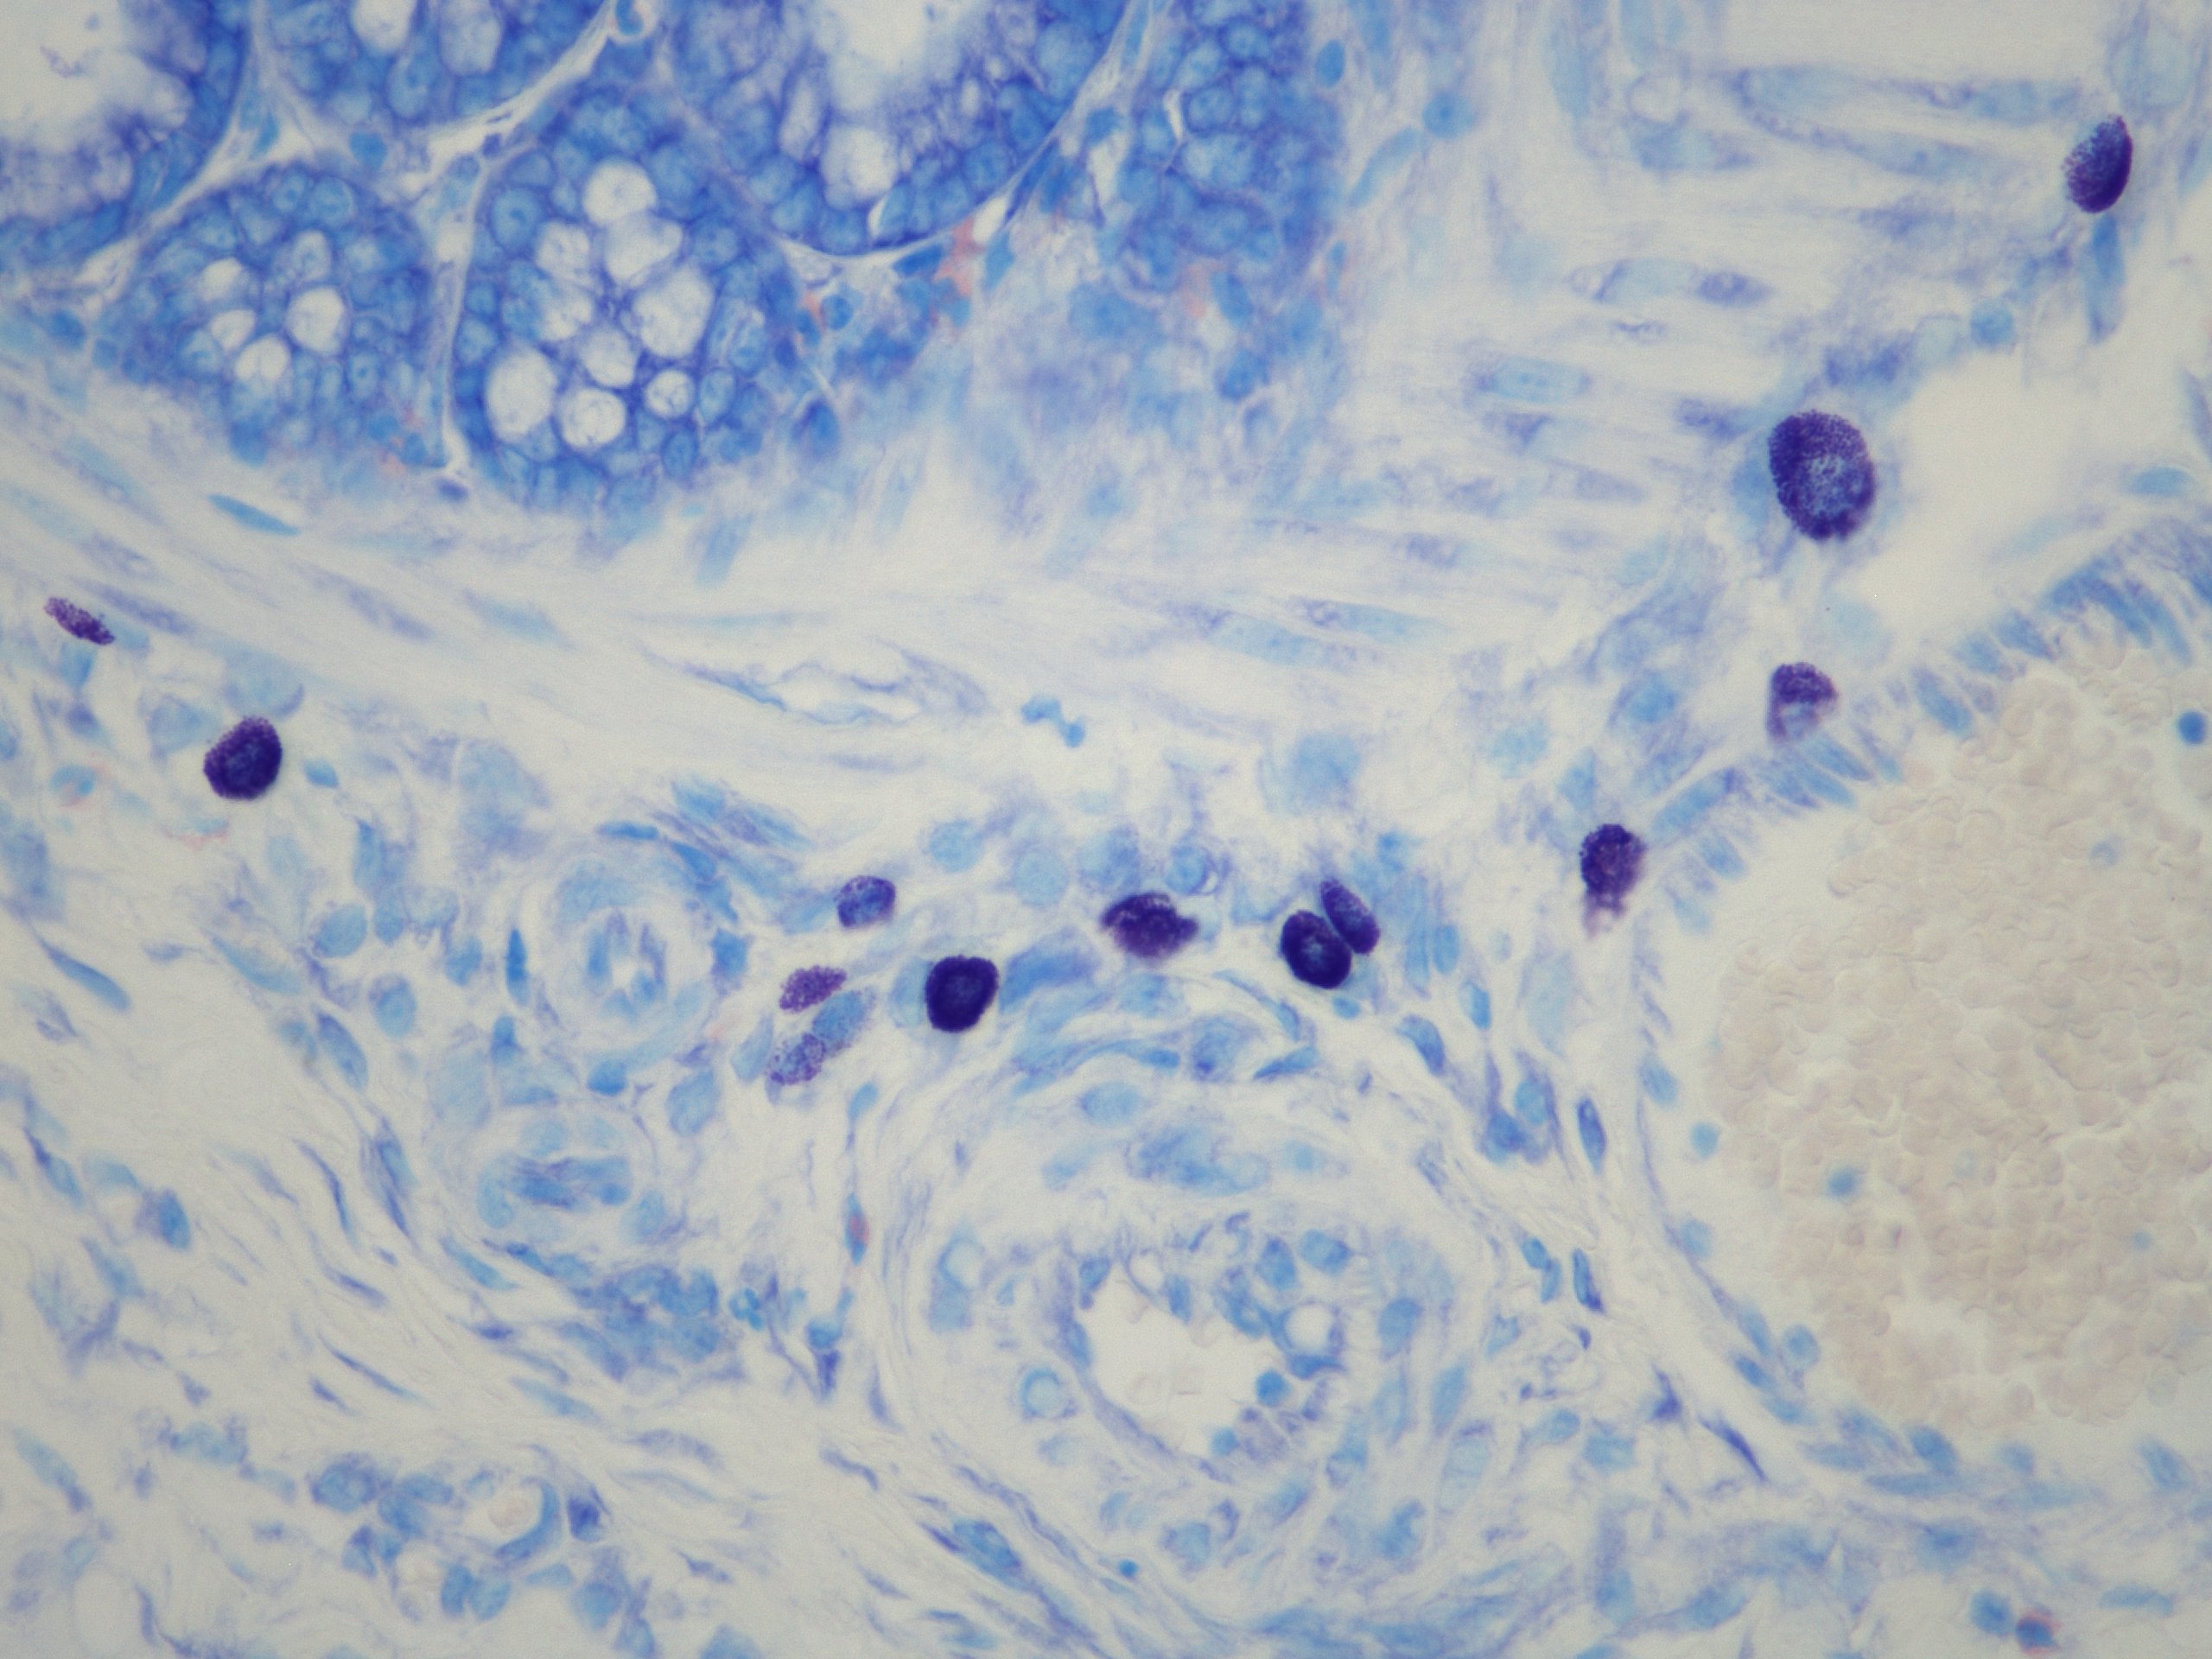

Mastociti (viola) in sottomucosa di colon.

Per gentile concessione della Dott.ssa Elena Lucarini, PostDoc, Università di Firenze (NEUROFARBA). © Epitech Group SpA